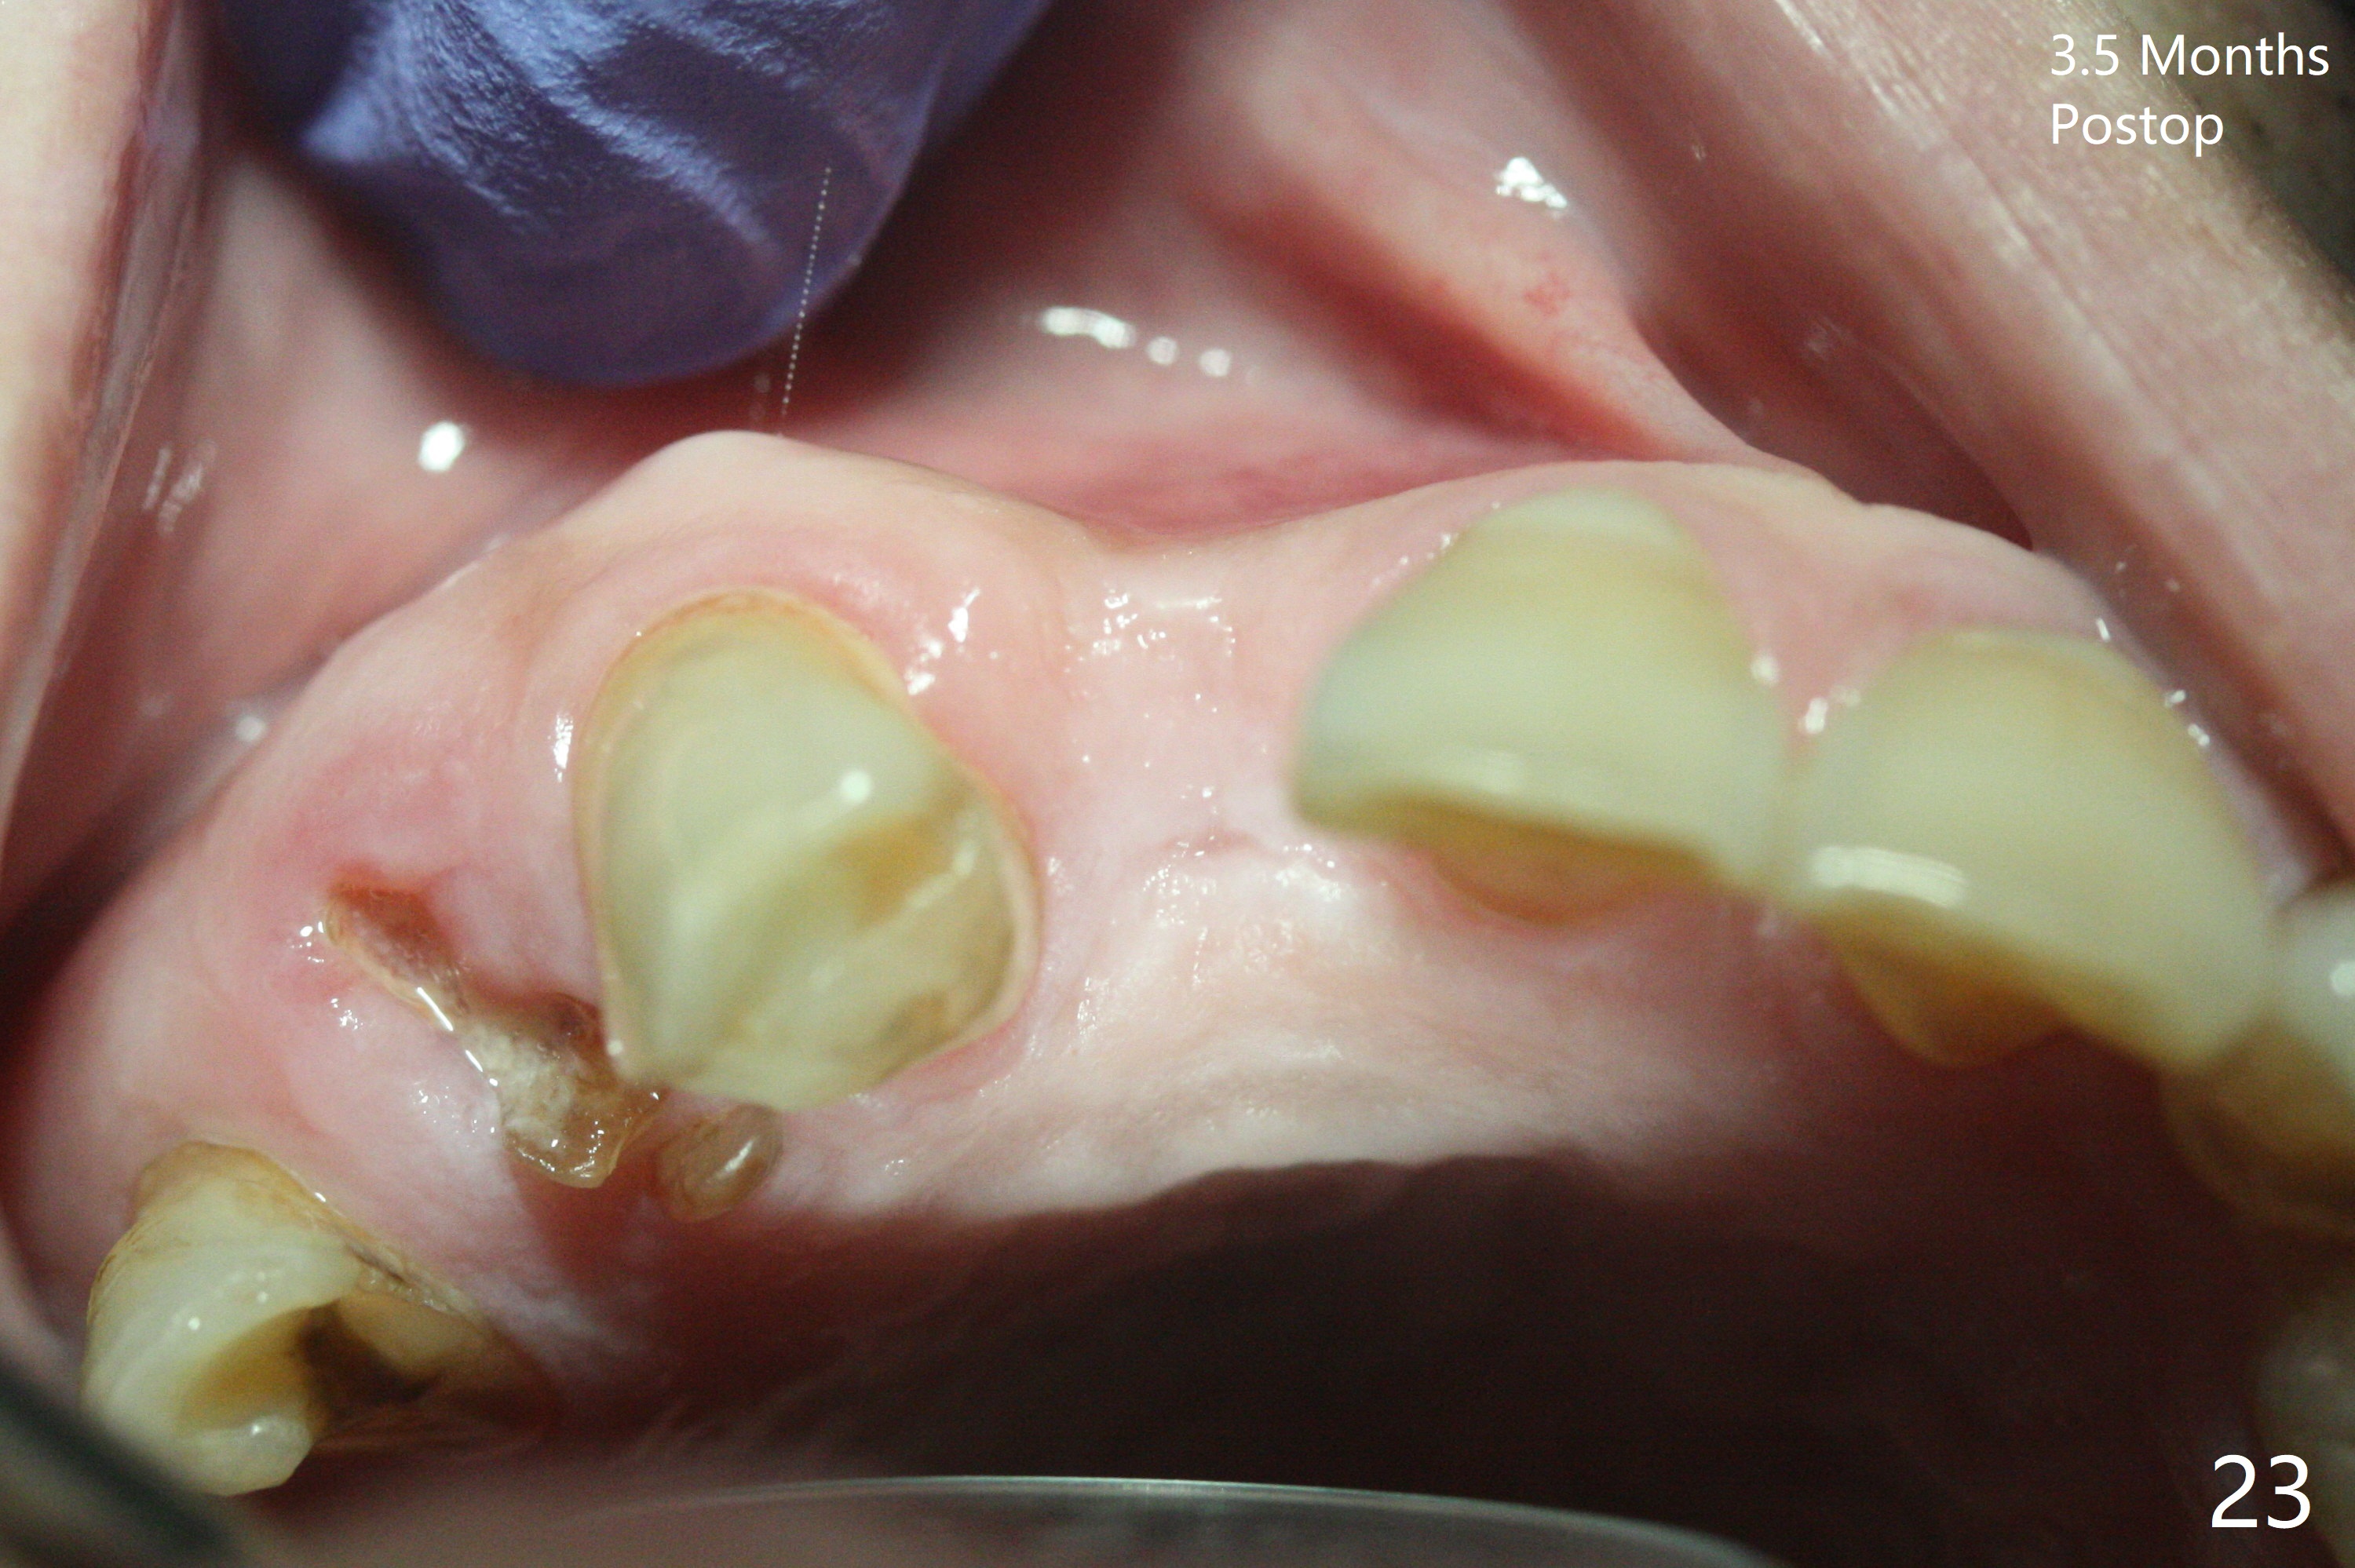

An apical abscess is present when the patient returns for immediate implant at #7 (Fig.1 *); a 2nd challenge is deep bite. After smooth extraction, the apical buccal plate is found to be perforated. Following debridement, a piece of gauze is placed in the apical defect for hemostasis, while osteotomy is initiated palatal (Fig.2). The apical defect seems to be extensive (Fig.3 yellow dashed line). A new trajectory is intended (red arrow) without much success. Before implant placement, bone graft is placed in the apical defect defect area, while a drill (Fig.4 D) is inserted in the finished osteotomy (Fig.5 O). In spite of seemingly large apical defect, the buccal crest bone exists (Fig.4 x). A 3x14(2) mm 1-piece implant is placed with stability; the first round of bone graft is apparently around the apical portion of the implant (Fig.6 *). The coronal end of the implant has to be adjusted several times buccopalatally to accommodate the deep bite. A 2nd round of bone graft following an immediate provisional closes the coronal space of the socket (Fig.7 *). CT will be taken to show the bone graft to repair the buccal plate defect when the patient returns for postop follow-up. In fact the defect is minimal in CT a month ago. The fistula does not disappear 1 week postop, but it is non tender (Fig.8). The patient complains of asymptomatic swelling in the right nostril. CT shows that the large buccal perforation is repaired with large amount of bone graft (Fig.9,10 *). It would be nicer to place the implant slightly more buccal apically (Fig.11 red lines; Fig.12 (preop design)). The buccoapical fistula disappears nearly 1 month postop (Fig.13). The apparently "lifeless" bone graft seems to be harmonious with the surrounding tissue (Fig.14). The periimplant gap reopens with implant mobility nearly 4 months postop (Fig.15), which is related to micro-movement associated with the immediate provisional. The latter is removed. A larger 2-piece implant will be placed in a 2-staged manner if needed (Fig.16). In fact the 3x14 mm straight 1-piece implant (Fig.17) has no mobility when it is retightened, but the trajectory remains buccal. Incision shows that there is no implant thread exposure. A 3x14 mm 15 degree angled 1-piece dummy implant is able to establish the correct trajectory, but there is no occlusal clearance (Fig.18). Micromovement during osteointegration may recreate loosening. Finally using Lindamann bur, the osteotomy is changed so that a 3.5x13 mm 2-piece implant does not need an angled abutment to establish occlusion (Fig.19). There is one palatal thread exposure. Allograft is placed circumferentially, followed by Human Amnion-Chorion Allograft and Collagen Plug. The wound does not heal 8 days postop (Fig.20), as related to the age (79 years old)? The wound appears to heal with a membrane on the surface (Amnion-Chorion one?) 3 weeks postop (Fig.21). The ridge looks wide 3.5 months postop (Fig.22,23). A 4.5x5.5(3) mm appears to be seated incompletely with a gap between the abutment and the implant (Fig.24<). A provisional is fabricated after heavy palatal reduction. Two months later, the provisional fractures. After repositioning the abutment with complete seating and torque (Fig.25), impression is taken. Although the buccal plate is concave, the gingiva remains healthy 10 months post cementation (Fig.26,27).